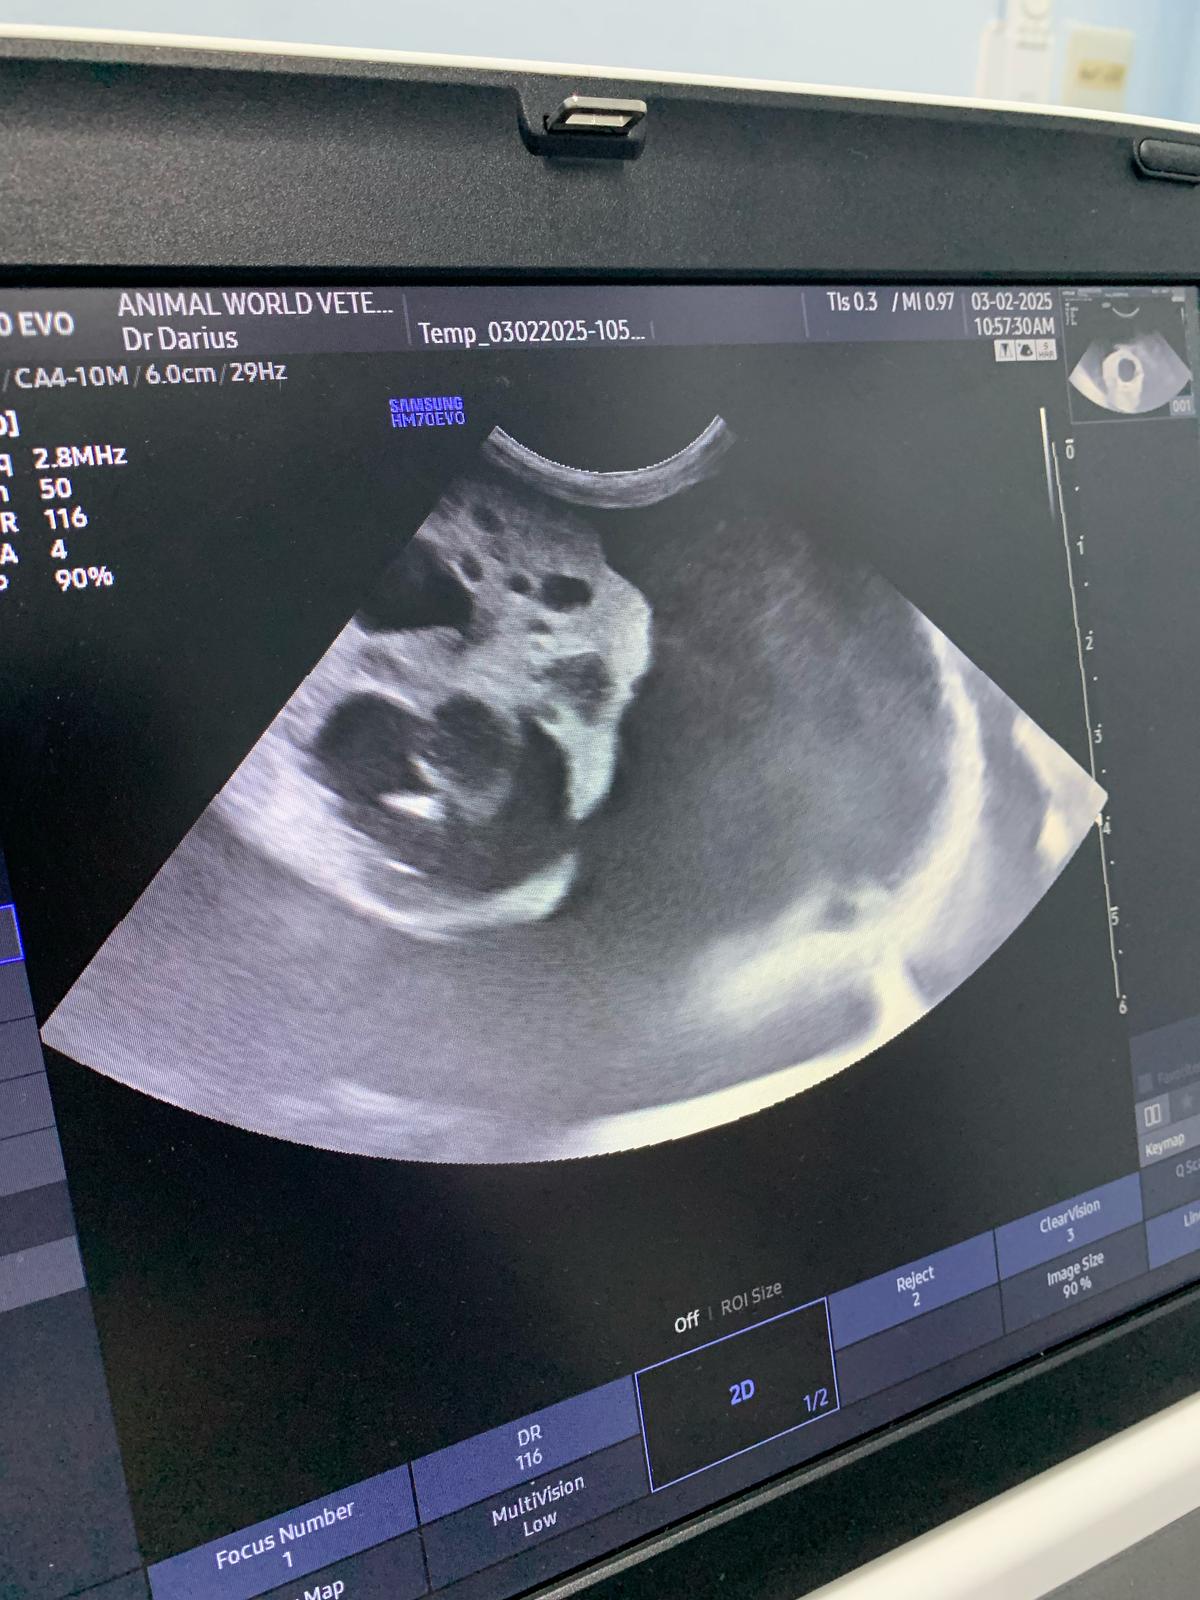

Dr d says she show dr ym aw u/s pic and she Duno what it is, meant be the shots r bad or what. They will do it at their end.

10.33am: dr d show me an u/s says don don kidney r the worst she had ever see, full of cysts for both kidneys. She remember Raichu so this family has a bad gene of cysts issue pass down. Don fluid r ard the kidneys, not the same as norm cats who had fluid ard the intestine, she said dr ym says it’s the same as last time, so she is confident of tapping, will do it away fr the kidneys. But the tapping won’t stop the cyst from leaking again. (Dr d mention more them twice that cysts r painful) noted that the tapping is more benefial to don don, only damage is my pocket) and the coming back is next time biz (maybe monthly tapping see how first).

Dr told me to go in to see her scan – both kidneys irregular in shape, like got holes like that (pic la, but he got multiple cysts on his kidneys) liver ok.